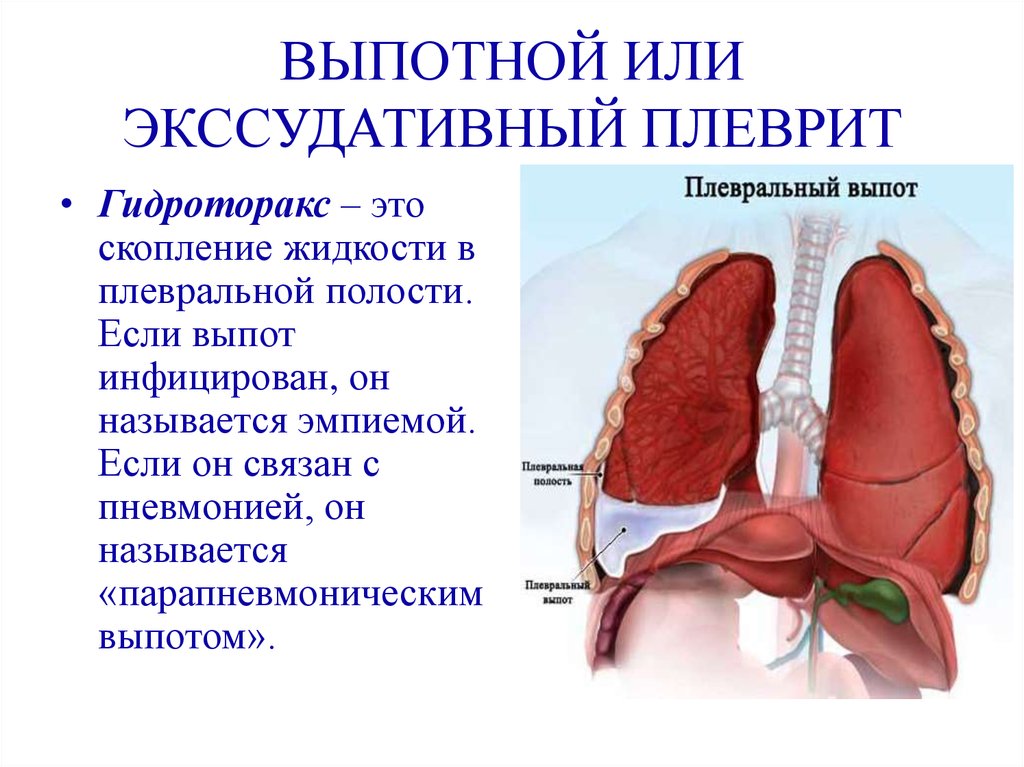

Симптомы и причины скопления воды в легких